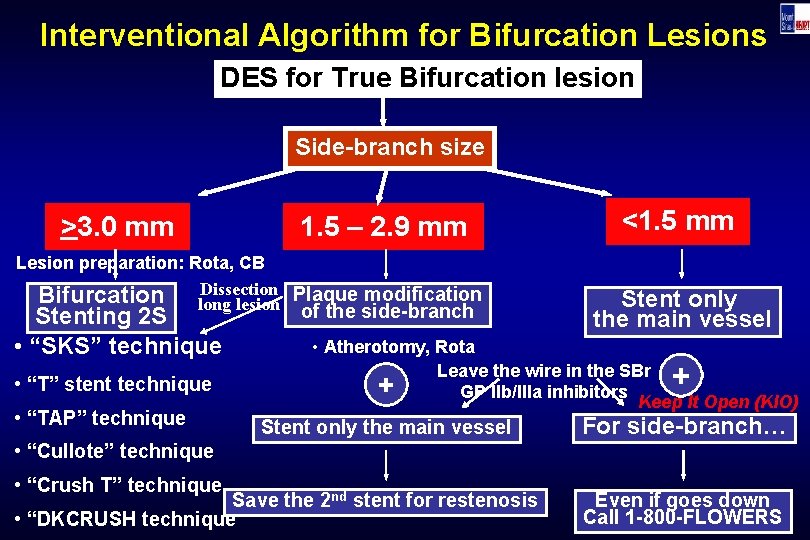

Interventional Algorithm for Bifurcation Lesions DES for True Bifurcation lesion Side-branch size >3. 0 mm 1. 5 – 2. 9 mm Lesion preparation: Rota, CB Dissection Plaque modification Bifurcation long lesion of the side-branch Stenting 2 S • “SKS” technique • “T” stent technique • “TAP” technique <1. 5 mm Stent only the main vessel • Atherotomy, Rota Leave the wire in the SBr + GP IIb/IIIa inhibitors Keep It Open (KIO) + Stent only the main vessel For side-branch… • “Cullote” technique • “Crush T” technique Save the 2 nd stent for restenosis • “DKCRUSH technique Even if goes down Call 1 -800 -FLOWERS